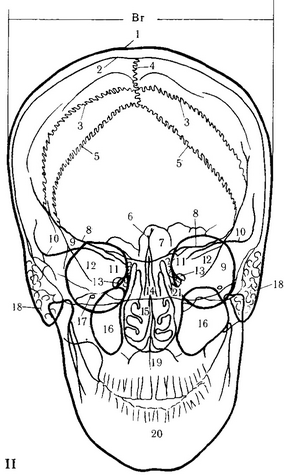

65. Передня оглядова рентгенограма черепа (по Л. Д. Линденбратену).

1 - зовнішня пластинка; 2 - внутрішня пластинка; 3 - вінцевий шов; 4 - сагітальний шов; 5-ламбдовідного шов; б - лобовий гребінь; 7 - лобові пазухи; 8 - верхні краї малих крил; 9 - скроневий край великого крила клиноподібної кістки; 10 - верхні краї пірамід скроневих кісток; 11 - верхівки пірамід; 12 - орбіти; 13 - отвір каналу зорового нерва; 14 - носова перегородка; 15 - носові ходи; 16 - верхньощелепні пазухи; 17 - подглазнічное отвір; 18 - соскоподібний відросток; 19 - верхня щелепа; 20 - нижня щелепа; 21 - клітини гратчастого лабіринту.